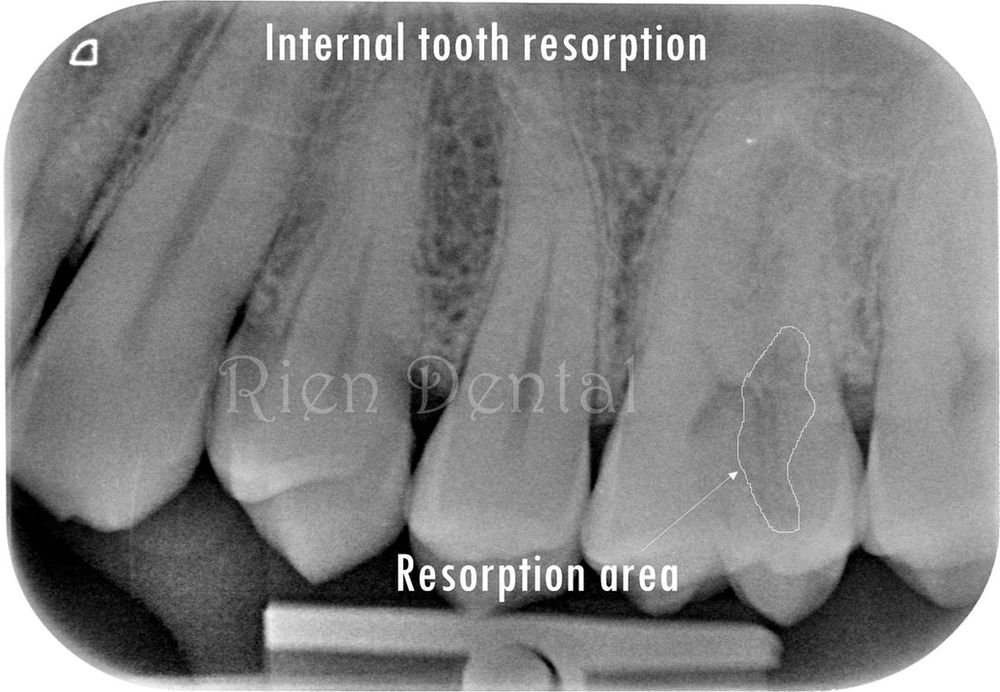

From www.riendental.com.au

Internal tooth resorption root canal treatment with 5 canals. How Long Does Tooth Resorption Take However, as resorption worsens, symptoms. Tooth resorption doesn’t always present a clear set of symptoms. If the teeth are a little loose and. It depends on how severe the trauma was, when it happened, how long the resorptive tissue has been there (and where) and the overall. But don’t condemn the tooth; There’s a lot that can be done to. How Long Does Tooth Resorption Take.